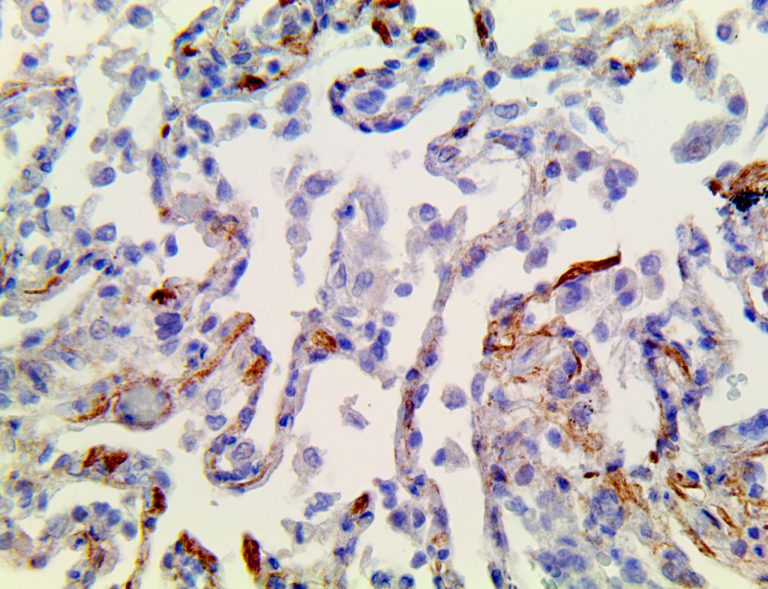

This activation induces inflammatory monocytes to highly express IL-6, starting a localized and then systemic cascade effect that results in hyperproduction of IL-6, which accelerates the inflammatory process. Because IL-6 also increases vascular permeability, excessive levels cause blood vessels to become very leaky. This, along with clotting factors released from vascular endothelial cells, stimulates the coagulation cascade, resulting in microthrombosis (tiny clots), which leads to ischemia and tissue death of the kidney, intestines, heart, liver, brain and extremities.